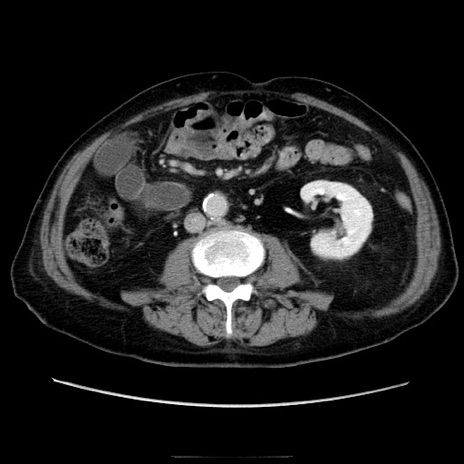

冠状断像

【症例】70歳代男性

【主訴】腹痛

【現病歴】肝硬変・肝細胞癌にてかかりつけの方。約9時間前に食後より腹痛出現。症状が徐々に増悪し、嘔吐出現したため来院。

【既往歴】肝硬変、肝細胞癌(RFA、TACE後)

【身体所見】意識清明、表情苦悶様、BT 36℃、BP 129/78mmHg、P 88bpm、SpO2 97%(RA)、右上腹部から心窩部にかけて圧痛あり、反跳痛なし、筋性防御あり。

【データ】WBC 5800、CRP 0.16